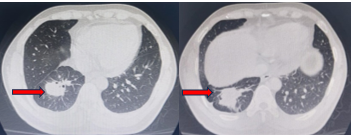

Chụp cắt lớp vi tính lồng ngực 1/10/2019 (sau điều trị)

Hình 4:Hình ảnh khối u thùy dưới phổi Phải giảm kích thước đáng kể sau điều trị (mũi tên)